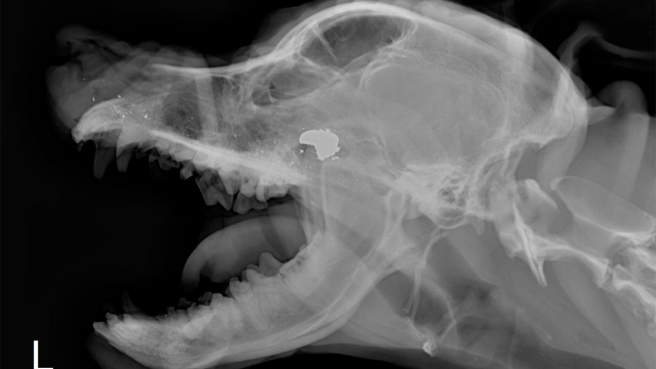

Contenido multimedia principal Mascota recibió impacto por arma de fuego por parte de un vigilante en Ibagué El animal tuvo que ser sometido a cirugía para salvarle la vida.